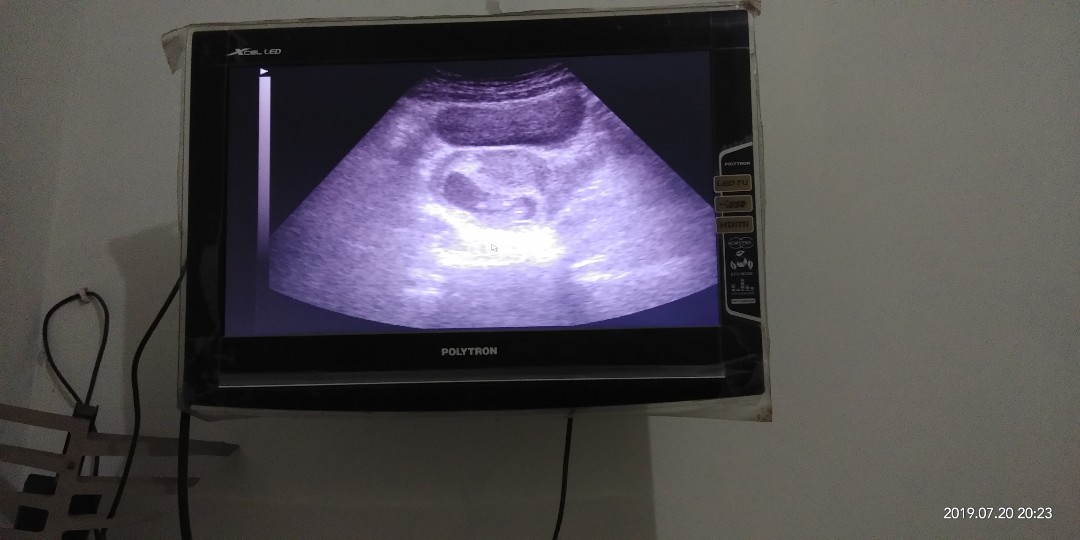

usg

10w

Ini